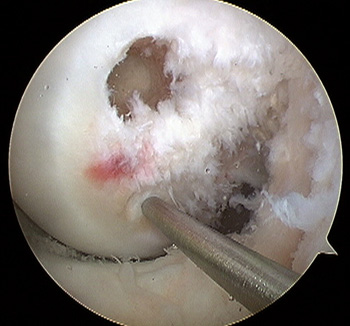

maestu1_fig3

Figura 3: vista artroscópica desde portal anterolateral del túnel anterolateral y marcado del túnel posteromedial en una rodilla izquierda.

maestu1_fig4

Figura 4: vista artroscópica desde portal anterolateral de túneles femorales para bandas anterolateral y posteromedial en una rodilla izquierda.